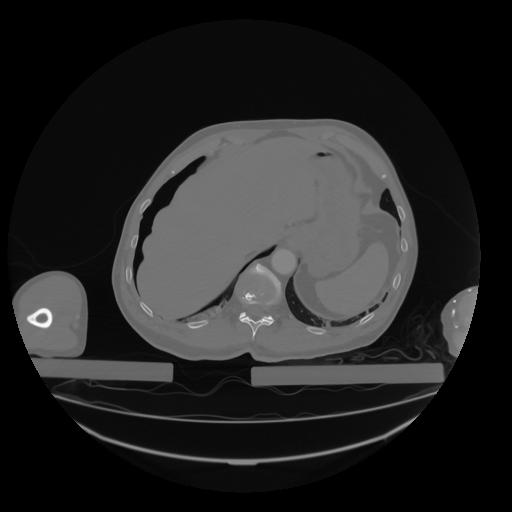

28 CUERPO,CE,Vol,2.0,CUERPO,,